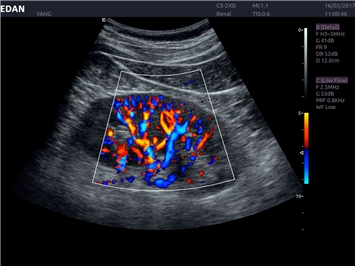

• 3D/4D-визуализация с автоматическим редактированием объема (eFace)

Трехмерная реконструкция ЦДК:

Да

Энергетический допплер:

Цветовой допплер:

Color 3D: